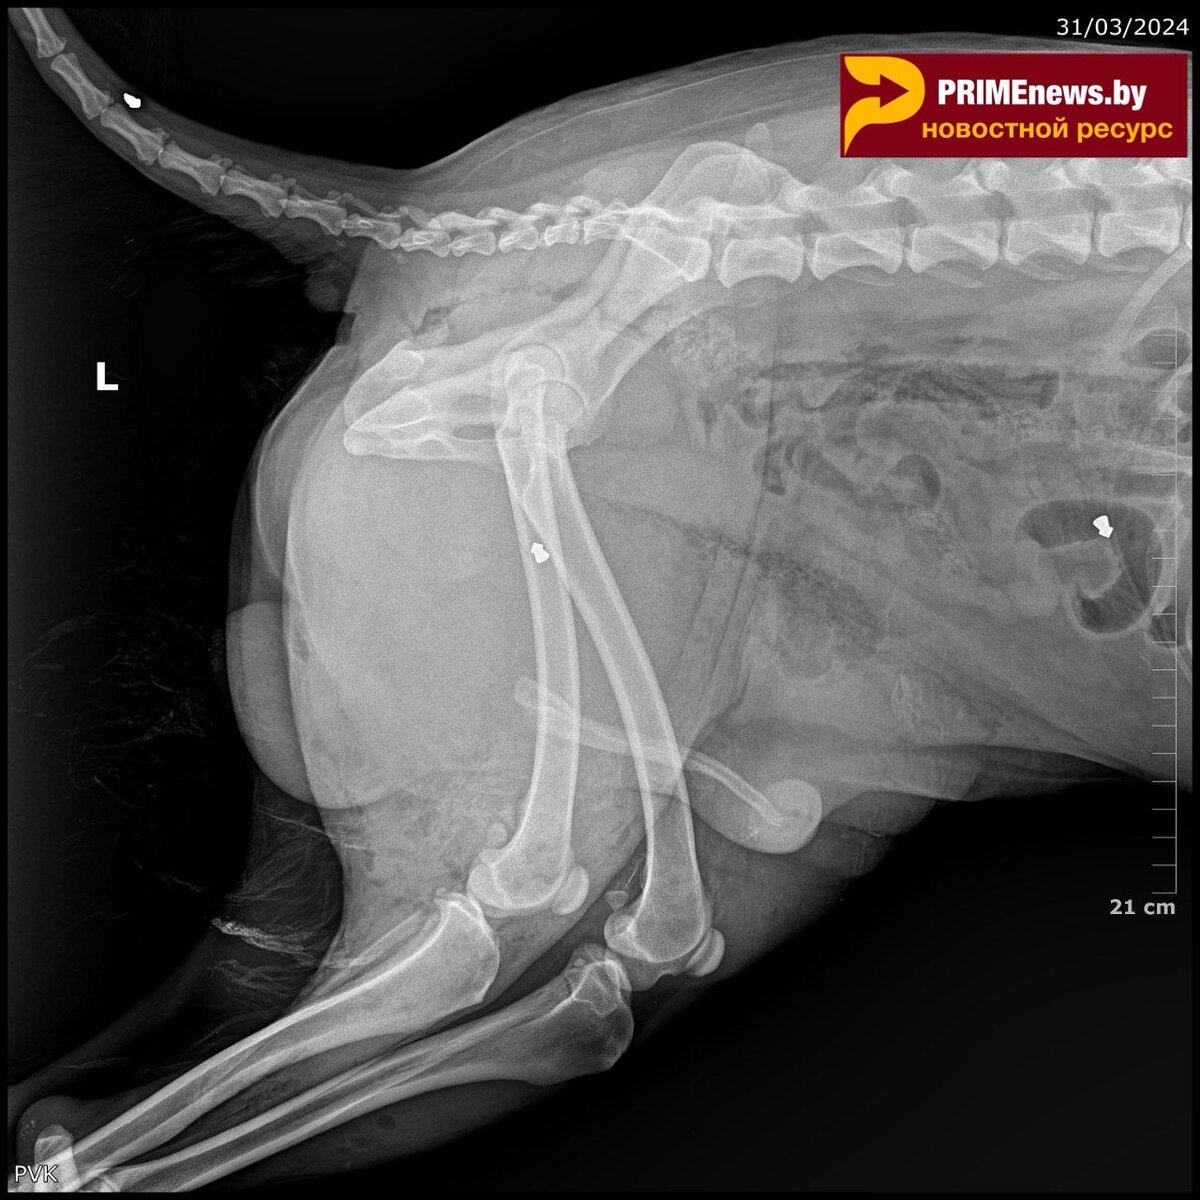

Как стало известно “Prime News”, 31 марта в Речице на АЗС номер 23 по Светлогорскому шоссе речичанами была обнаружена раненая собака. Неравнодушные горожане связались с волонтёрами социально-благотворительного учреждения “Дом с хвостом”. Пёс был доставлен в ветклинику города Гомеля, где скончался практически по приезду от полученных ран. По рентген-снимкам было определено, что в собаку стреляли (дроби в области брюшины, бедра и хвоста) и смерть наступила от большой потери крови. Волонтёры “Дом с хвостом” написали заявление в правоохранительные органы. Следственный комитет возбудил уголовное дело по статье “Жестокое обращение с животным”.

По рентген-снимкам было определено, что в собаку стреляли (дроби в области брюшины, бедра и хвоста) и смерть наступила от большой потери крови.